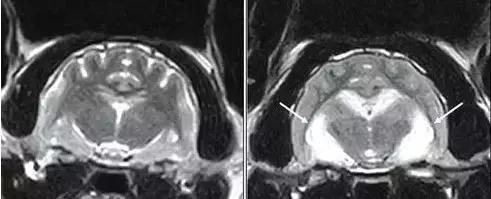

左图:MRI扫描正常的猫大脑

右图:疑似癫痫诱发脑损伤(海马坏死)的猫大脑(白箭头所指)

图中患猫表现为急性全身性癫痫发作和行为改变,包括攻击、流涎和方向迷失